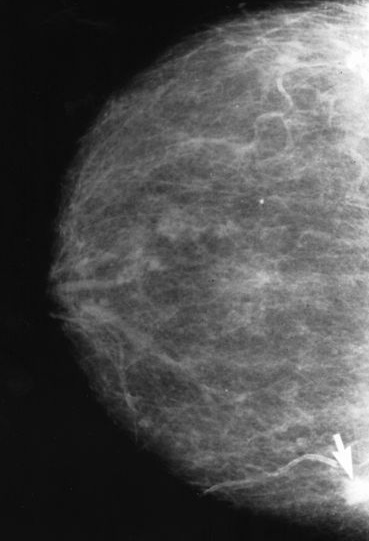

Cardiac Symptoms & Breast Cancer

Bizath Taqui, MD; Himani Shishodia, MD; Ronald N. Rubin, MD

Anthracyclines are the most common cause of cardiovascular complications in patients with cancer.